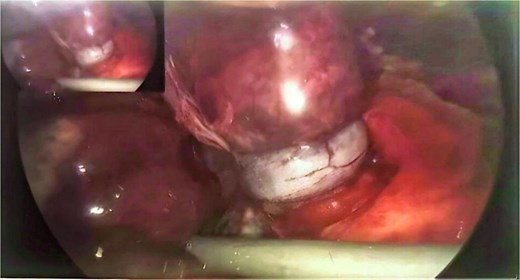

We present a case of a 76-year-old gentleman who had a previous elective laparoscopic TAPP right inguinal hernia repair in another hospital on January 2023. The procedure reportedly went well with no complications. The patient then presented on March 2023, 2 months after his procedure, with symptoms of small bowel obstruction. The initial computed tomography (CT) scan showed high-grade small bowel obstruction (Figs 1 and 2). The patient was initially treated conservatively as for most cases of small bowel obstruction thought to be attributed to adhesions from recent surgeries. The decision was made to take the patient for a diagnostic laparoscopy 48 hours after conservative management failed to resolve symptoms. Laparoscopically, gross small bowel ischemia was noted, and a tube-like structure was seen wrapping around the ischemic segment (Figs 3 and 4). The decision was taken to convert the procedure to an open one due to massive bowel dilatation and the inability to define the nature of this adhesive wrap. Upon conversion, it was noted that this tube-like structure causing the band was indeed the appendix wrapping around the terminal ileum, with its distal part adhered to the eroded mesh from the peritoneal flap of the recent TAPP repair. The decision was taken to perform a limited ileocecal resection and primary anastomosis. The protruding part of the mesh was excised, and the appendix resected. The peritoneal flap was closed with sutures. The patient did very well postoperatively and was discharged a couple of days later.

Operative image showing appendix wrapped around and constricting the terminal ileum (taken with permission).